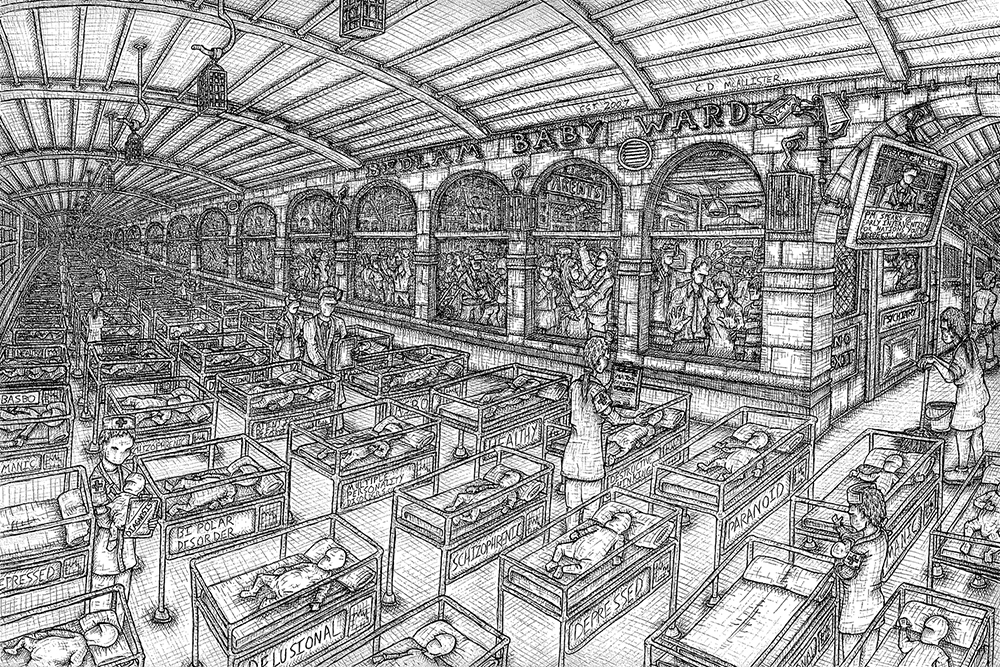

#2 "Bedlam Babies" 2007 (Sold)

Technical pen on paper. 12 H x 16 W in.

Commissioned by CSIP - Care Services Improvement Paternership to highlight the stigma of mental health diagnosis at a young age.

Signed limited edition Giclée prints available. (£100) 12 H x 17 W in.